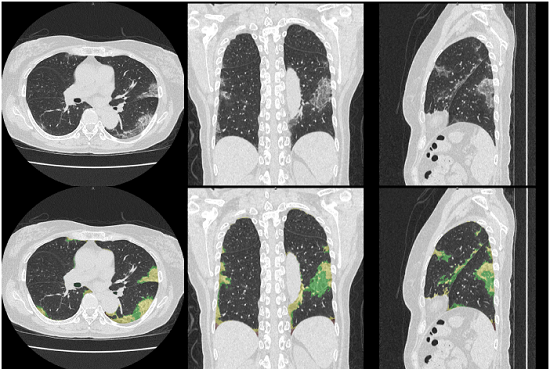

今回の適用評価で用いるびまん性肺疾患を中心としたCTテクスチャー解析は、藤田医科大学 大野良治教授とキヤノンメディカルが産学共同研究で開発した技術である。本解析技術は、CT画像を用い、様々な肺疾患の結果生じる肺の陰影・形状情報から、正常肺、すりガラス影、浸潤影、蜂巣肺、粒状影や気腫性病変など、肺の7種類の形態的特徴を、機械学習によって識別し定量化するものであり、基礎的な研究成果はすでに各種学会で報告され、間質性肺炎の重症度と解析による定量的な結果に相関があること発表実績1~2)、放射線科医と解析による所見の一致度が十分であること発表実績3~4)が示されている。2020年7月末から本解析技術を用いて新型コロナウイルス肺炎疑いの症例を解析し、臨床への適用評価を進めていく。

各種肺疾患を対象にしたCTテクスチャー解析技術を用いることにより、

1. 医療機関を受診した無症状やPCR陰性新型コロナウイルス肺炎患者の検出

2. 新型コロナウイルス肺炎とその他の感染症との鑑別診断に難渋する患者における診断精度向上と適切な医療提供

3. 定量的CT所見評価に基づく発症後経過期間推定や重症度評価と効率的な治療法選択補助

4. 定量的CT所見評価による治療効果判定に基づく患者マネージメント補助